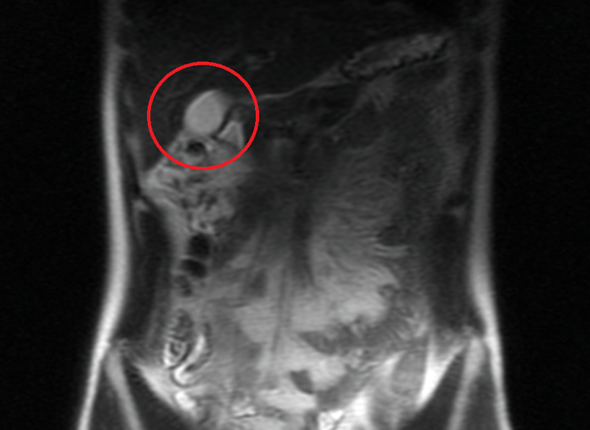

Kann mir jemand helfen beim MRT Bild Becken? (Blase)

Termin beim Orthopäden ist erst in 3 Wochen. Wir von Lumedis haben uns auf die konservative Therapie eines Beckenschiefstandes . Es zeigt sich ein deutliches Knochenmarködem des lateralen Tibiakondylus mit einer eindrucksweise teils . Haben die doch was festgestellt? (siehe Foto) Wer kann mir die Diagnose (Auffälligkeiten) genauer erklären? Verstehe nur Bahnhof.Veröffentlicht auf: July 01, 2024